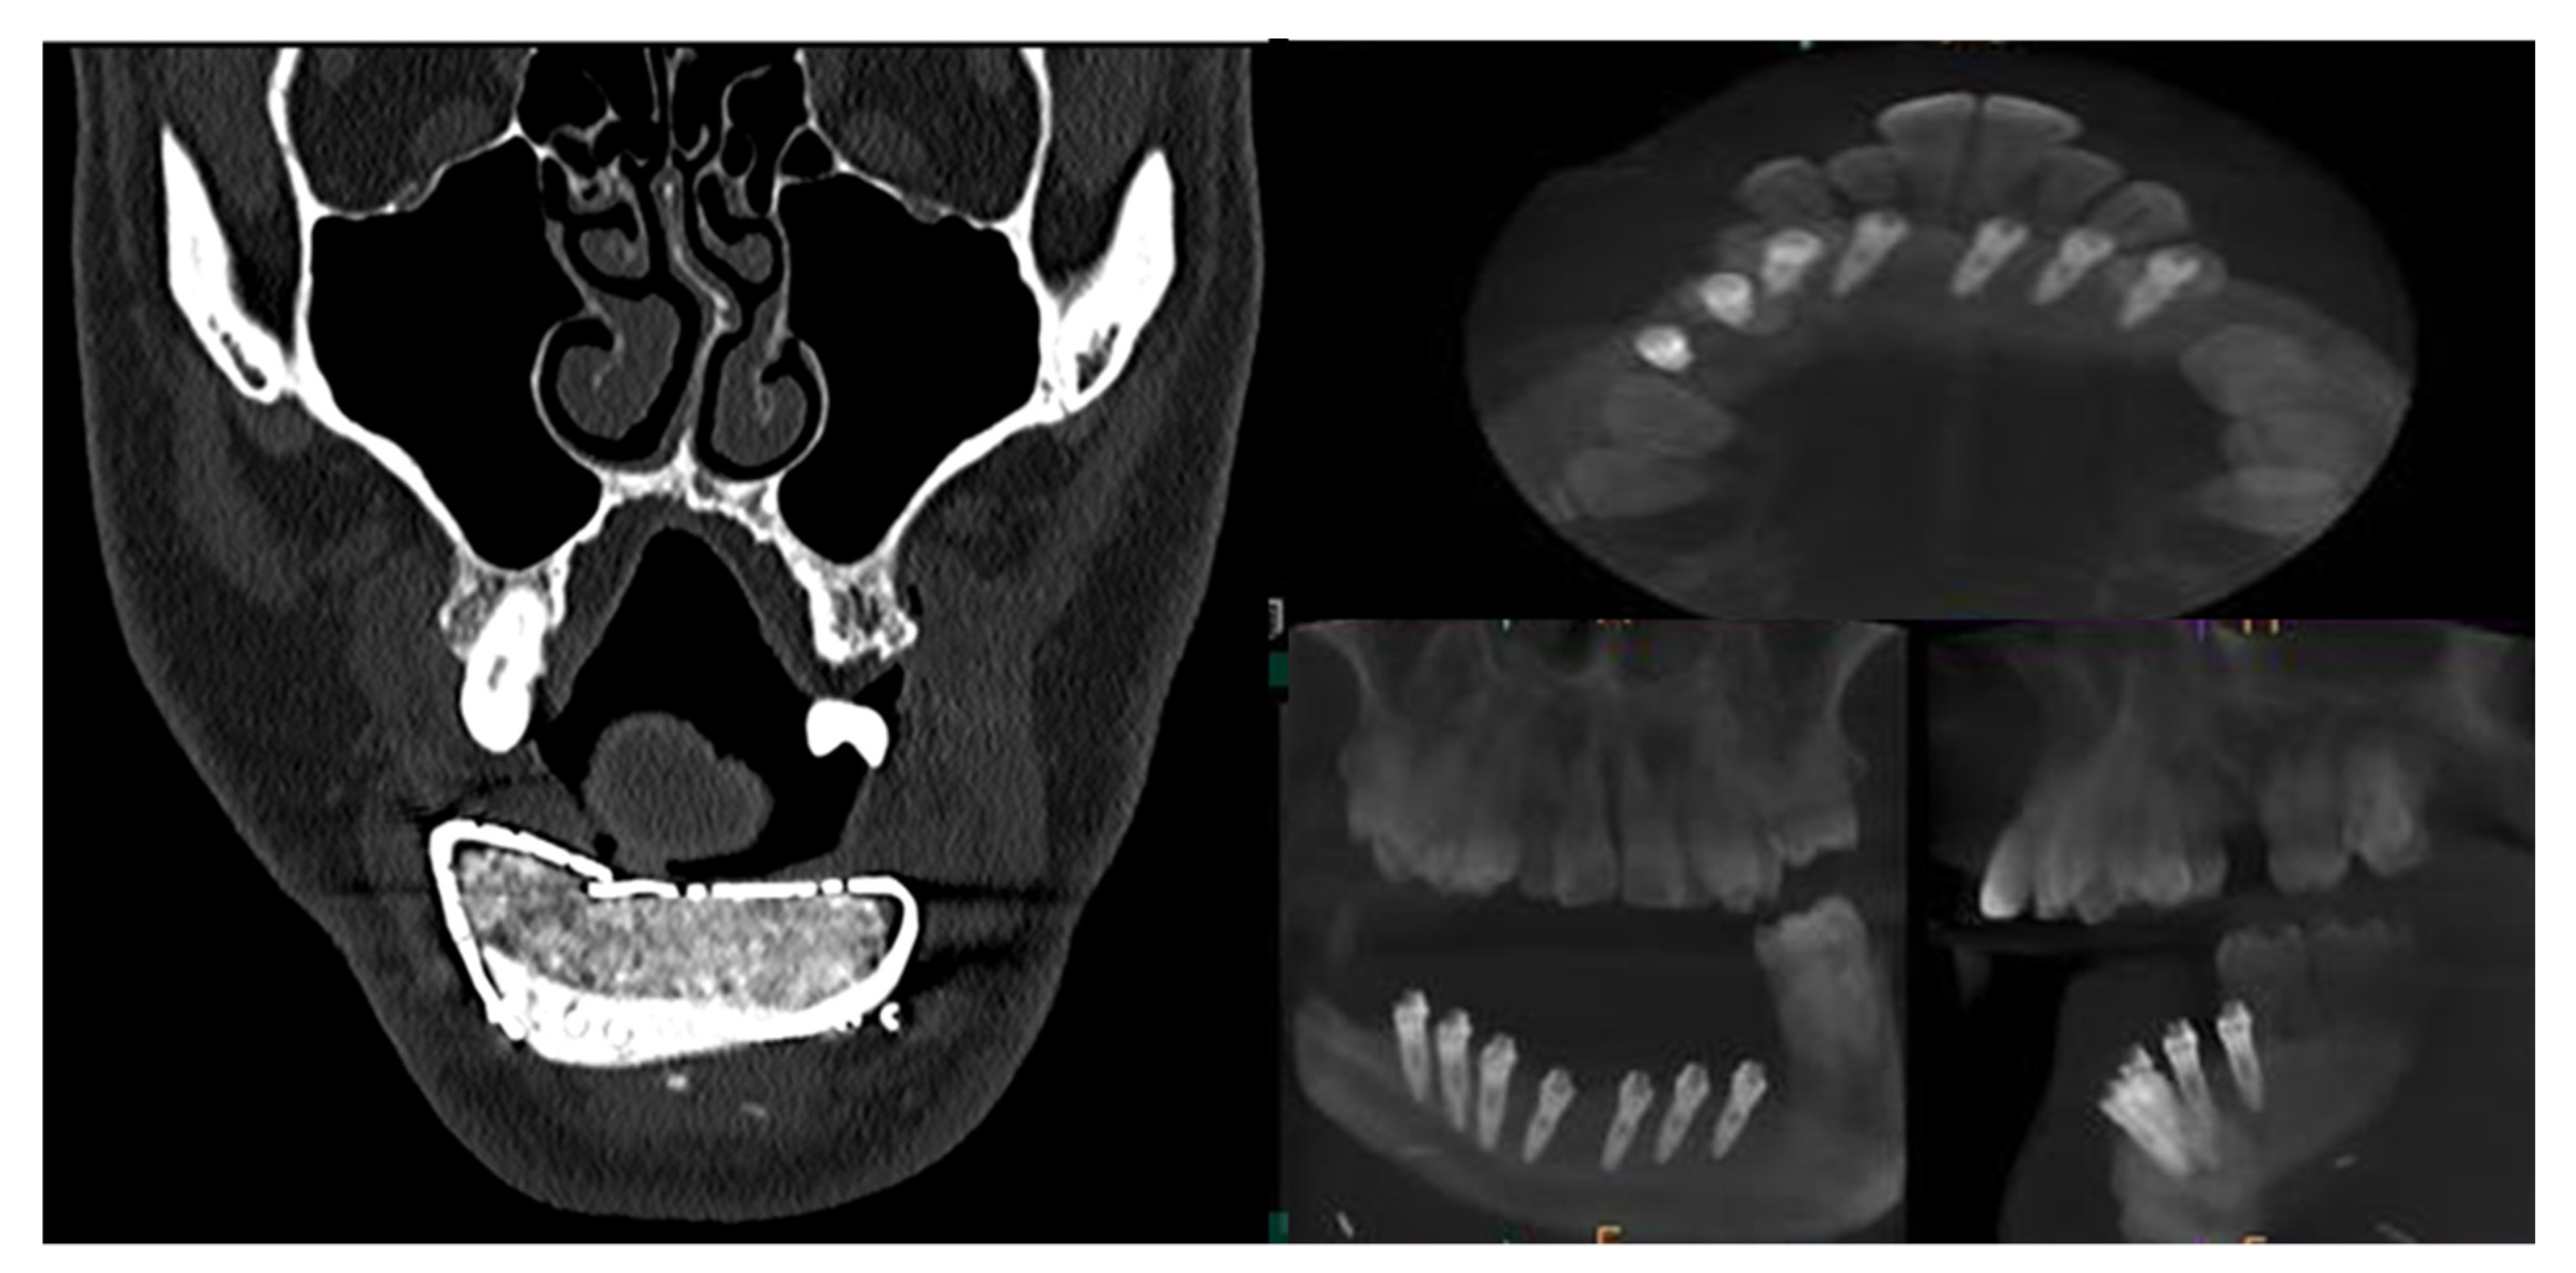

CT Scan and CBCT were performed in the postoperative follow-up, and bone volume and bone resorption (Figure 13 and Figure 14) were evaluated by the Radiology Department of the hospital. A morphing reconstruction was performed to compare the lower facial third showing an improvement in the aesthetic profile and facial projection (Figure 15).

Figure 13. CT Scan and CBCT were performed in the postoperative follow-up, providing relevant quantitative data regarding bone volume and bone resorption.

Figure 14. CBCT performed in the follow-up to evaluate bone resorption before and after implant loading.